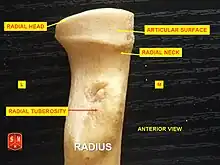

L'épiphyse proximale du radius est constituée de la tête présente une tête du radius, du col du radius et de la tubérosité du radius.

Tête du radius

La tête du radius est une saillie cylindrique au sommet du radius.

Sa face supérieure présente une surface articulaire de faible concavité, la facette articulaire de la tête du radius qui s'articule avec le capitulum de l'humérus pour former l'articulation huméro-radiale. Le point le plus profond de cette cavité n'est pas axisymétrique avec le grand axe du radius, créant un effet de came lors de la pronation et de la supination.

La circonférence articulaire de la tête du radius est lisse et s'articule médialement avec l'incisure radiale de l'ulna pour former l'articulation radio-ulnaire proximale. Elle est embrassée par le ligament annulaire du radius.

Col du radius

Le col du radius est la partie cylindrique et rétrécie qui sépare la tête du radius de la diaphyse du radius. Sur sa partie postérieure une légère crête donne une insertion au muscle long abducteur du pouce.

Tubérosité du radius

La tubérosité du radius est une éminence ovoïde à grand axe vertical qui est situé en avant et médialement à la jonction du col et de la diaphyse du radius.

Sa partie postérieure rugueuse donne insertion au tendon du muscle biceps brachial.

Sa partie antérieure lisse est séparée du tendon par une bourse synoviale.